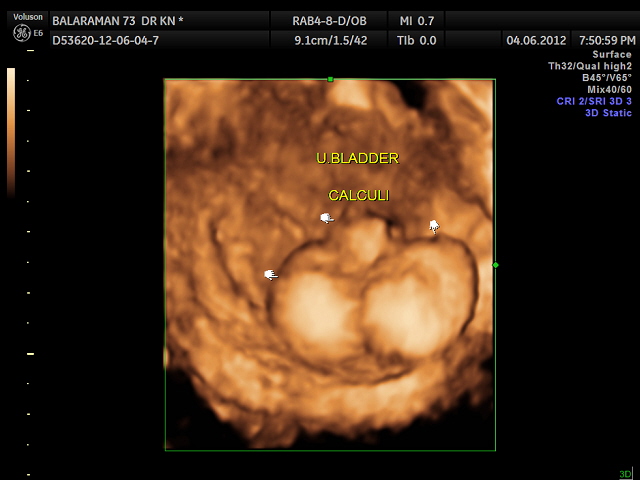

THIS WAS A 73 YEAR OLD MAN WITH DIFFICULTY IN PASSING URINE AND STRANGURY OF RECENT ONSET ; THE REFERRING PHYSICIAN WAS KEEN ON RULING OUT ANY PROSTATIC PATHOLOGY.

USG SHOWED THIS